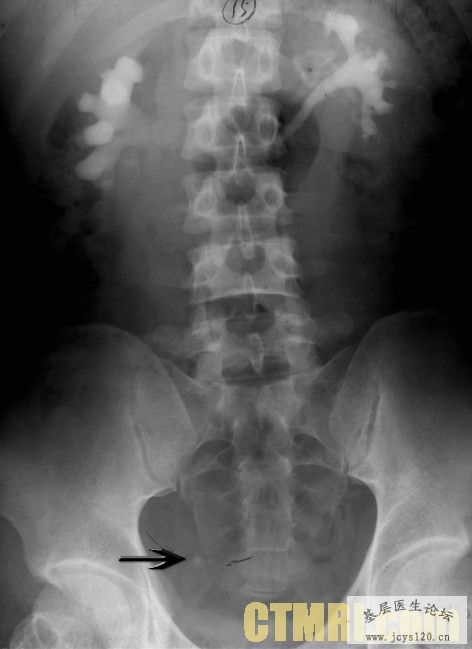

大家对这样的病有什么好的治疗方法吗 我的治疗是 肌注黄体酮 抗炎利尿扩张输尿管